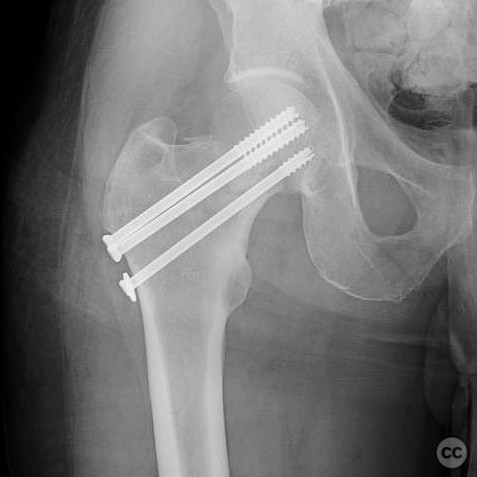

Anatomical surgical approach:  A percutaneous approach was utilized, involving small stab incisions for the insertion of guide wires and cannulated screws. Fluoroscopic imaging was employed to ensure proper alignment and fixation.

The surgeon emphasized the importance of achieving an anatomical reduction and avoiding varus malalignment during fixation. The decision to pursue percutaneous fixation was influenced by the patient's high risk for complications with arthroplasty due to his comorbidities and lifestyle factors. The potential for conversion to hemiarthroplasty was considered if fixation failed.

Postoperative protocol:   Postoperative rehabilitation included non-weight bearing on the affected limb for 6 weeks, followed by gradual progression to weight bearing as tolerated, contingent upon radiographic evidence of healing.

Orthopaedic implants used:   Cannulated screws